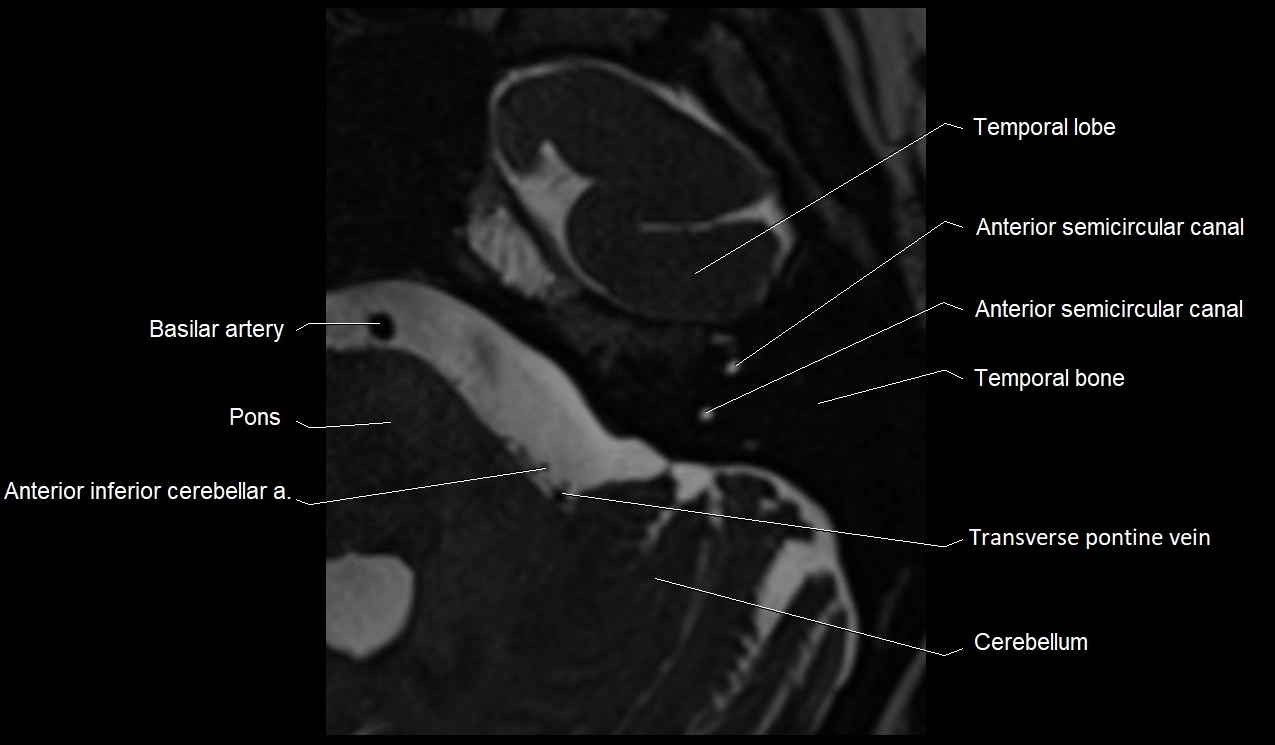

MRI images

image